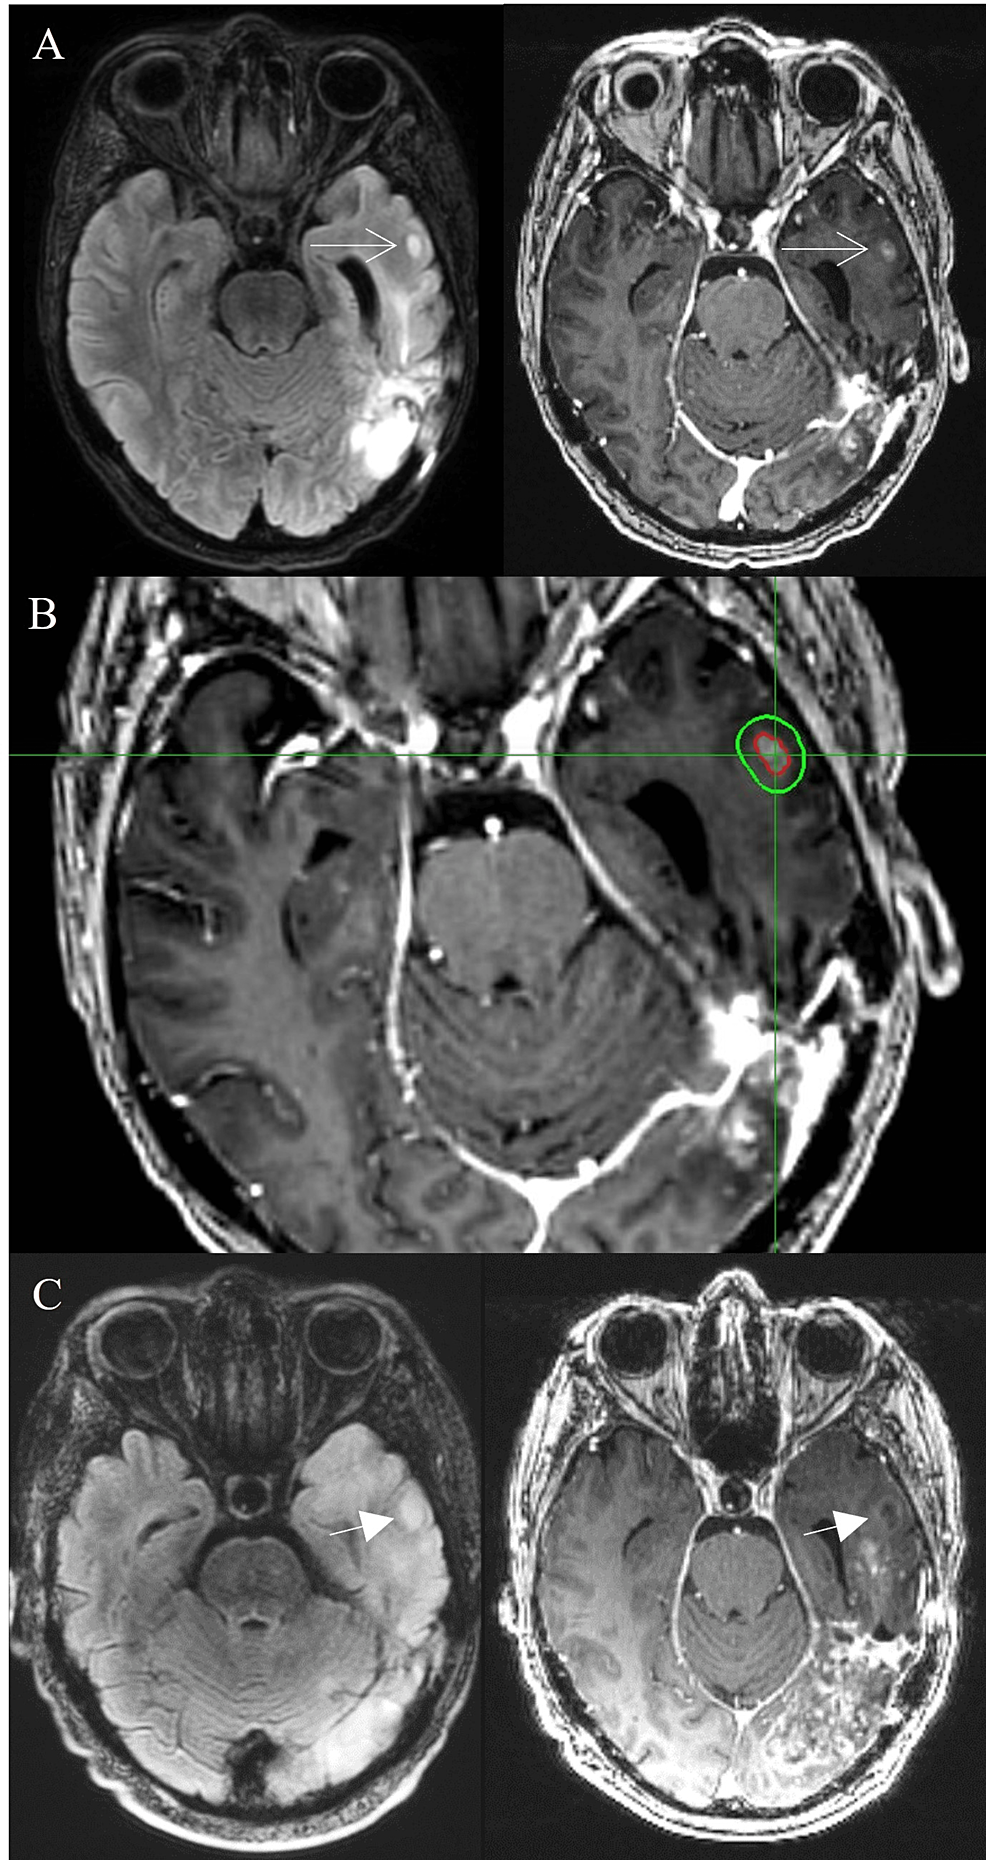

Cureus Stereotactic Radiosurgery for ContrastEnhancing Satellite Satellite Lesion Meaning The term clinical satellite or satellite metastasis refers to tumor located no further than 5.0 cm from the primary lesion, although in transit. In melanoma, satellite tumors occur. The term “satellite lesions” is used in many conditions in dermatology, generally to describe smaller lesions near the edges of a. Lesions occurring within 2 cm of the primary tumor are classified. Satellite Lesion Meaning.